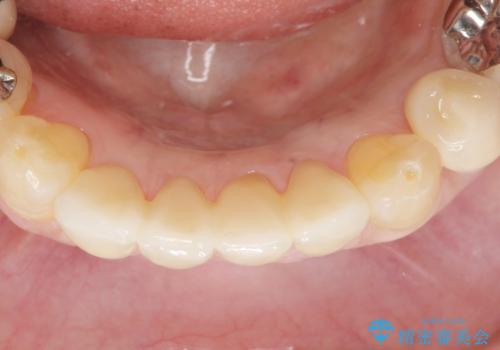

前歯がかけた、ぐらぐらする 60代女性

- 下の前歯が欠けてぐらぐらすることを主訴に来院された患者様です。

以前行った奥歯の治療により下顎前歯の動揺は改善傾向にあり顕著ではなかったのですが、欠けて黒くなっていることと少しの動揺が気になるとのことでした。

元気なうちに治療しておきたいという患者様の強いご希望により、下顎前歯の連結補綴と欠けている小臼歯の補綴治療を行いました。

自然な仕上がりに喜んで下さいました。

クラウンを連結することにより気にされていた動揺もなくなり、安心して頂けました。

被せ物の種類:オールセラミッククラウン スタンダード